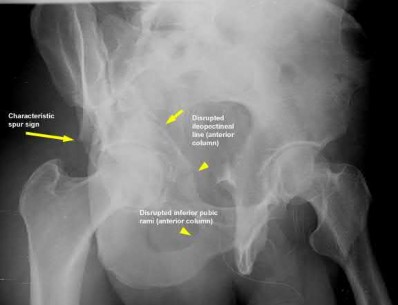

1007) The radiographic finding in Figure 58 is indicative of what type of acetabular fracture?

1. Anterior column

2. Posterior column

3. Associated both column

4. Transverse

5. Associated transverse plus posterior wall Corrent answer: 3

The radiographic image is an obturator oblique view of the left acetabulum and demonstrates a "spur" sign. It represents a spike of bone from the intact hemipelvis and no articular surface remains with the hemipelvis, which defines the associated both column fracture. The weight-bearing surface of the acetabulum is displaced with the femoral head. In all other patterns, at least part of the articular surface remains with the intact hemipelvis.

There are 5 simple and 5 associated fracture types according to the classification system created by Judet and Letournel. The key feature which distinguishes both column fractures from other associated types is that all articular segments are detached from the intact portion of the ilium, which remains attached to the sacrum through the SI joint.

Although the transverse plus posterior wall, T-shaped, and anterior plus posterior hemi-transverse fractures all show involvement of the anterior and posterior columns, they are not “both columns” because a portion of the

articular surface remains in its normal position, attached to intact ilium.

The intact ilium is responsible for the "spur sign" noted most prominently on the obturator oblique radiograph.

Illustration A demonstrates the 10 types of acetabular fractures as created by Judet and Letournel. Illustration B is an example of a both column acetabular fractures as seen on the obturator oblique radiograph.